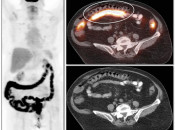

Misregistration

Because the resulting CT images and PET images will be fused, it is imperative that there be as little patient movement between the time of the CT scan and the PET scan, minimizing malalignment (“misregistration”) of the resulting images. This is especially difficult because the PET portion of the exam often requires the patient to remain still for up to 30 minutes.

While the hybrid nature of the machine and its shared patient bed certainly help to limit this malalignment of images, subtle unintended patient repositioning during the exam is a frequent occurrence.

Additionally, even when the patient remains perfectly still, bowel peristalsis over the 30-minute exam and respiratory motion regularly cause misregistration of the CT and PET images.